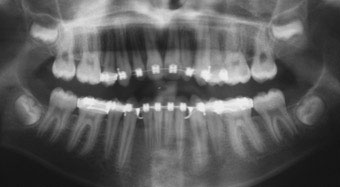

DIAGNOSTIC

Ce jeune patient présentait un schéma de classe I squelettique normodivergent (Fig. 1, 2, 3). Sur le plan occlusal, il présentait une classe 2 dentaire bilatérale, une biproalvéolie incisive sévère, une béance antérieure, ainsi qu’un articulé inversé entre 26 et 36. Les 12 et 22 étaient de taille réduite (Fig. 4, 5, 6).

Sur le plan fonctionnel, nous avons noté une succion du pouce nocturne, et une déglutition de type infantile avec interposition linguale.

Enfin, son profil était convexe avec une projection des tissus mous vers l’avant (Fig. 7, 8).